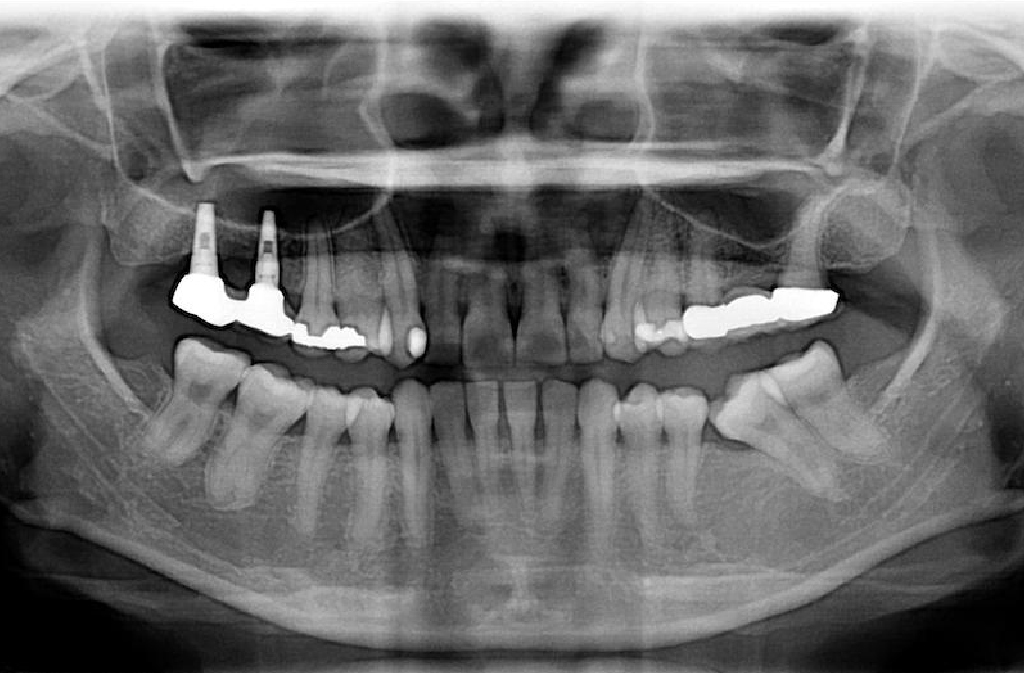

牙周病的檢查目的就是要了解患者牙周病的嚴重程度,以利訂定治療的計畫。檢查分兩項:第一項,測量牙周囊袋的深度,了解牙周病破壞的深度。第二項,拍攝全口X光片,了解牙齒周圍還剩多少骨頭,評估牙齒的預後。

探測牙周囊袋的深度

拍攝全口X光片

9. 牙周病患者適合植牙嗎?

• 牙周病並不是植牙的禁忌,只要能夠將牙周病控制穩定,植牙一樣能夠有很高的存活率。若因為先前的牙周病導致骨頭、角化牙齦的喪失,仍然可以藉由補骨、補肉的方式來彌補後天條件的不足。